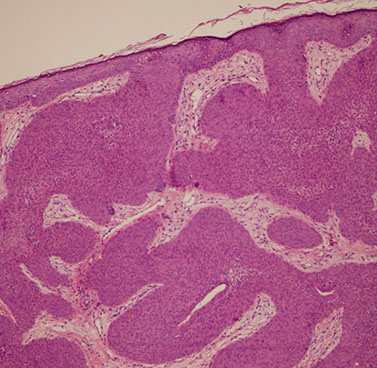

Syringocystadenoma Papilliferum (SCAP)

aka papillary syringadenoma

b9 sweat gland proliferation that arises in the middle of a nevus sebaceus

- warty tumor of scalp, neck, and face that can occur at any age

- clinically is a slow growing or recent change in a brithmark, may be crusty and start to bleed

- 1/3 have adjacent nevus sebaceus, 10% with adjacent BCC

- malignant counterpart is syringocystadenocarcinoma papilliferum

Micro: glandular papillary prolif connected to skin surface

- has ducts that look similar to sweat ducts sometimes, which are lined by cuboidal cells, that eventually empty to skin surface

- dense plasma cell infiltrate in the dermis, or in the middle of the papillary structures